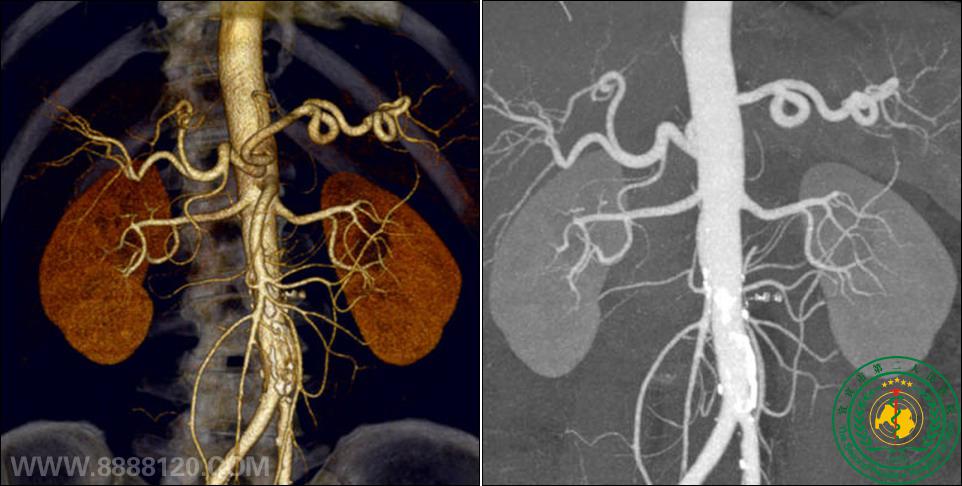

腹主动脉及其分支及双肾重建